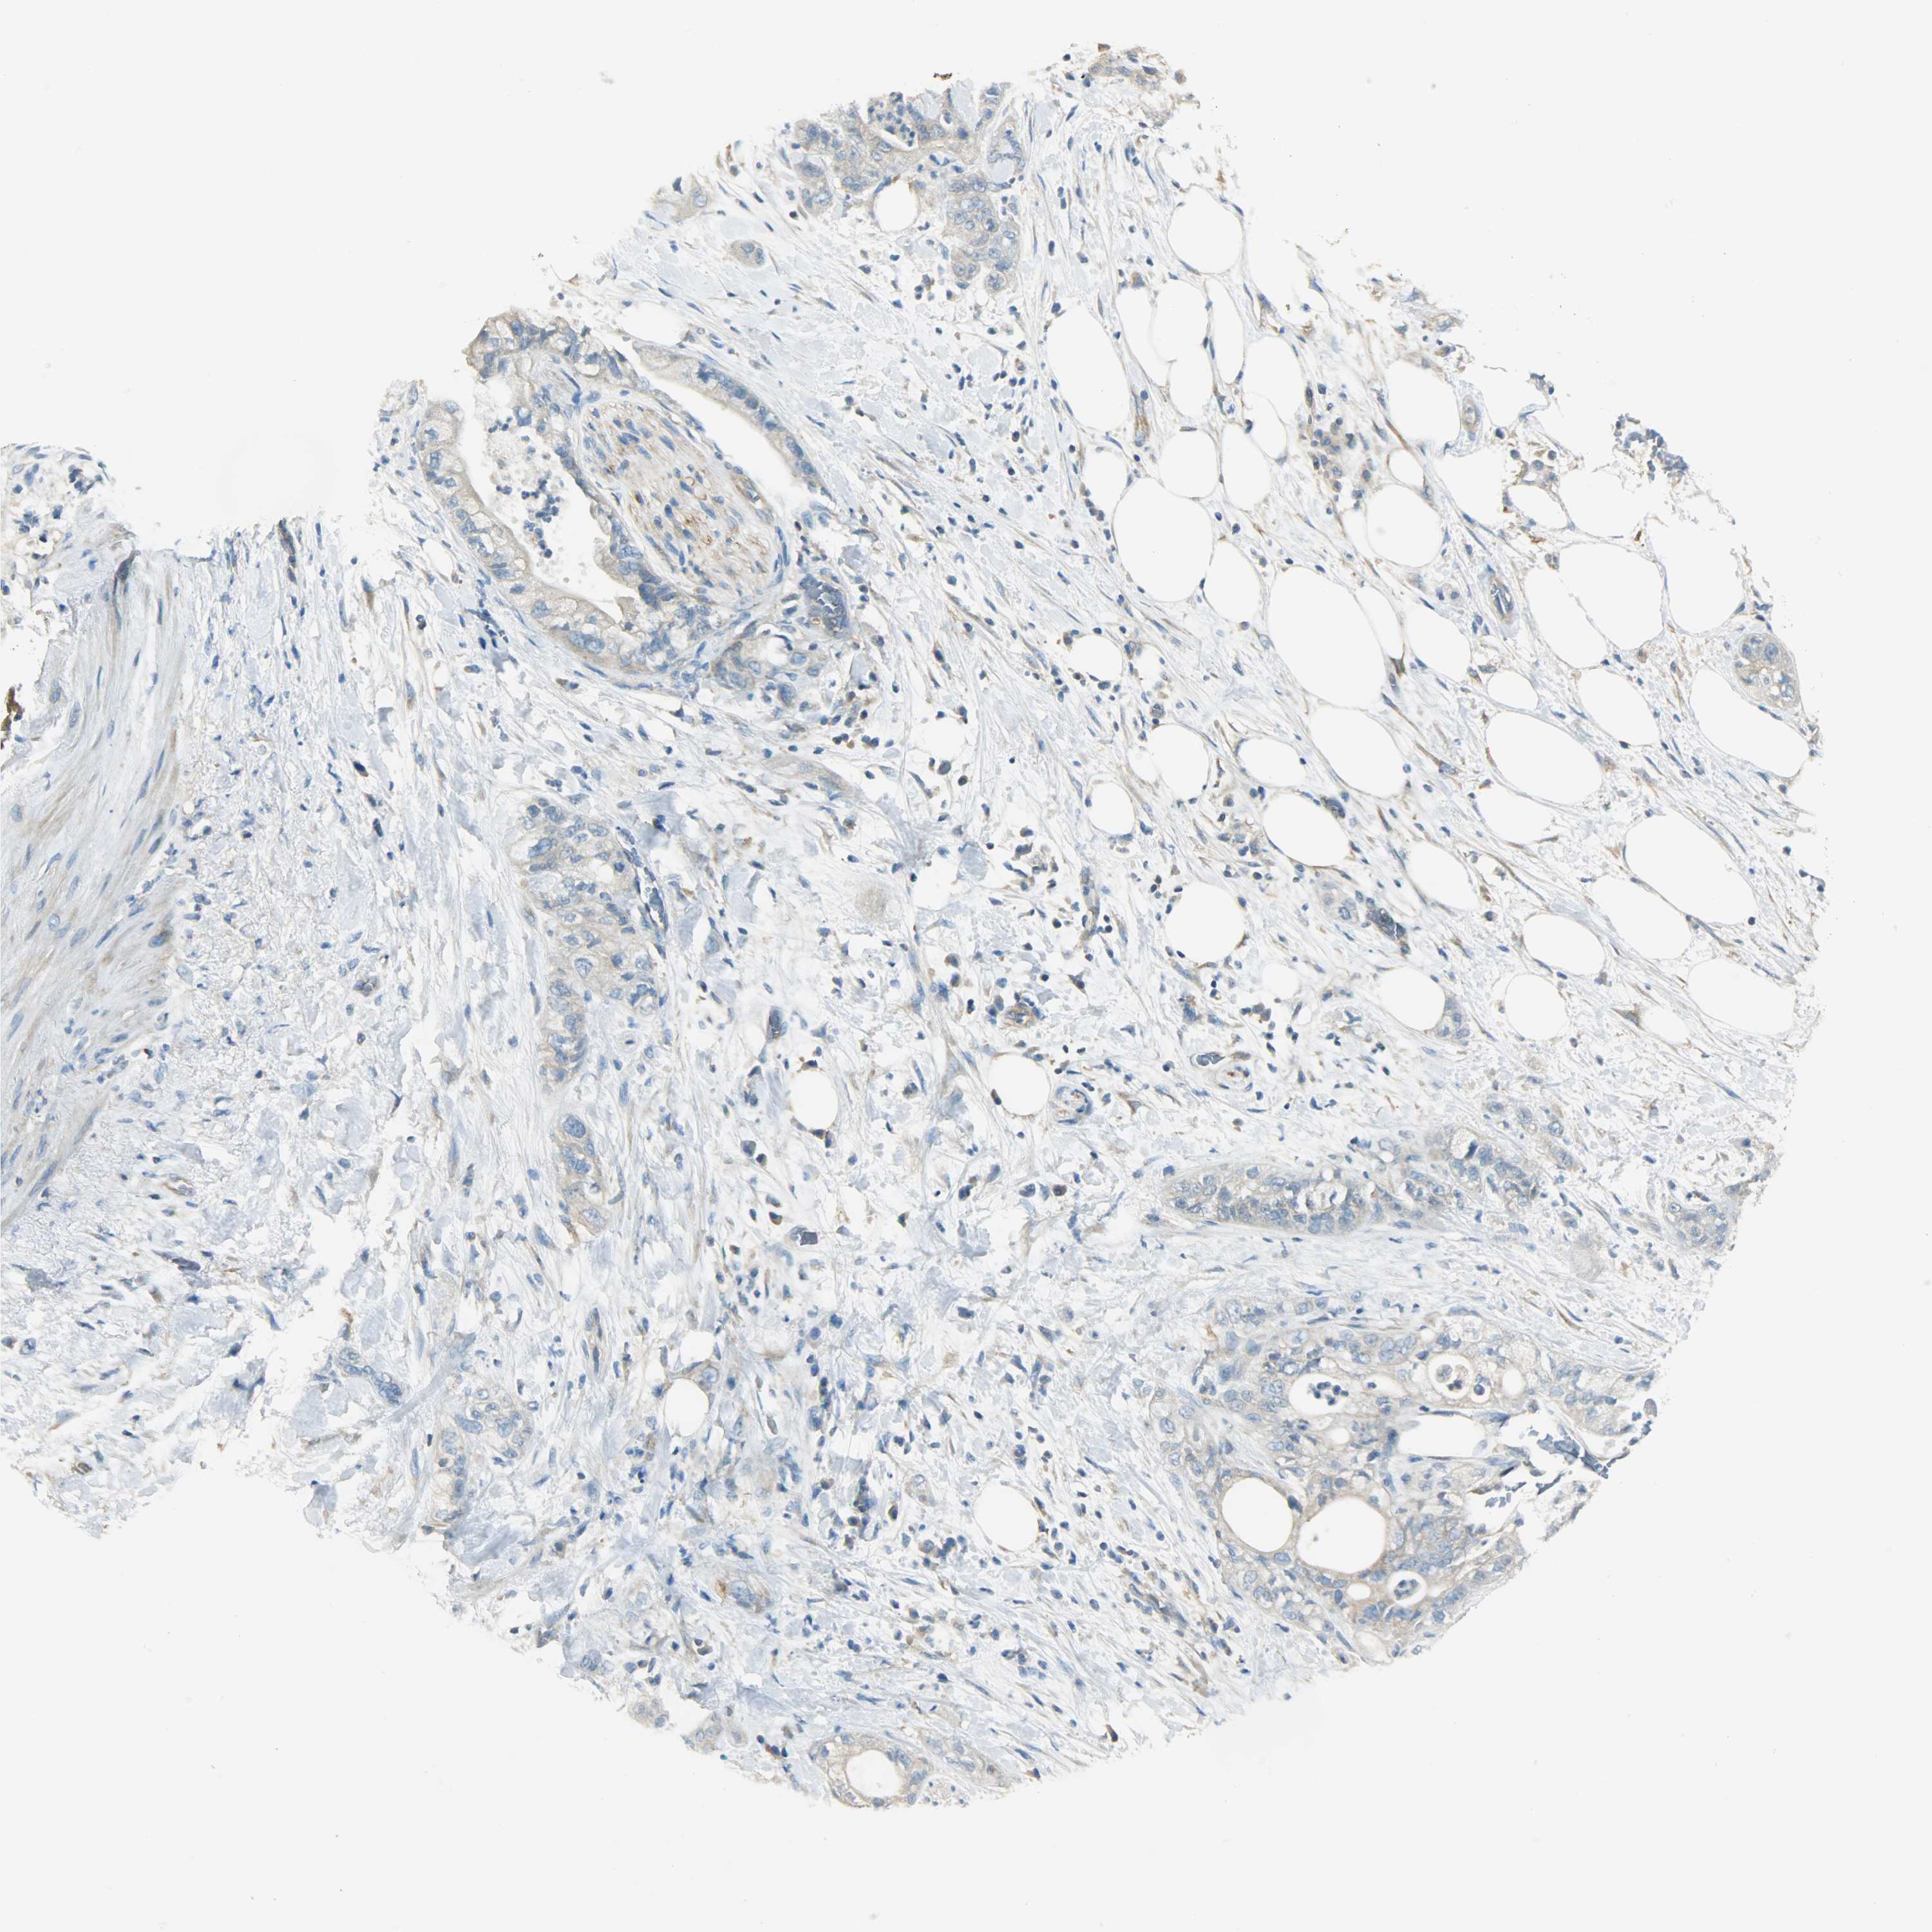

PANCREATIC CANCER - Protein expressioni

A mouse-over function shows sample information and annotation data. Click on an image to view it in a full screen mode. Samples can be filtered based on level of antibody staining by selecting one or several of the following categories: high, medium, low and not detected. The assay and annotation is described here.

Note that samples used for immunohistochemistry by the Human Protein Atlas do not correspond to samples in the TCGA dataset.

Antibody stainingi

Antibody staining in the annotated cell types in the current human tissue is reported as not detected, low, medium, or high, based on conventional immunohistochemistry profiling in selected tissues. This score is based on the combination of the staining intensity and fraction of stained cells.

Each image is clickable and will lead to virtual microscopy that enables deeper exploration of all samples and also displays staining intensity scores, fraction scores and subcellular localization as well as patient and tissue information for each sample.

Antibody HPA004926

Staining

High

Medium

Low

Not detected

Intensity

Strong

Moderate

Weak

Negative

Quantity

>75%

75%-25%

<25%

None

Location

Nuclear

Cytoplasmic/membranous

Cytoplasmic/membranous,nuclear

Adenocarcinoma, NOS

Adenocarcinoma, metastatic, NOS